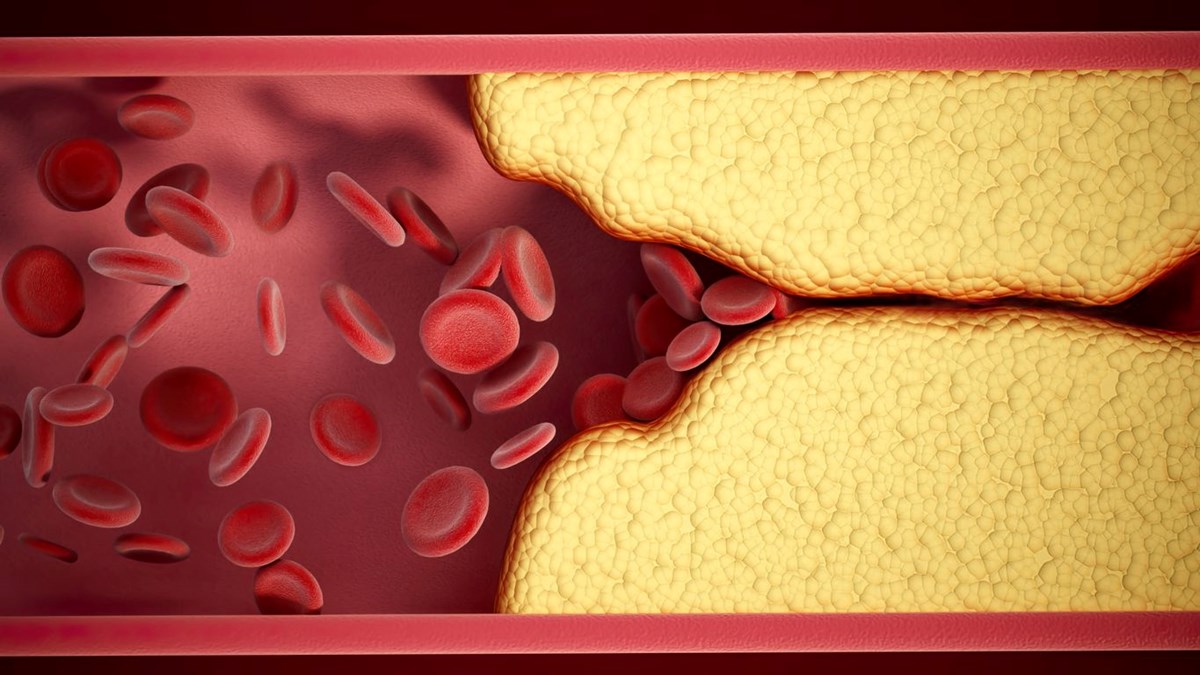

Kalp rahatsızlıkları riski her geçen gün artıyor ve buna en çok katkıda bulunan etkenlerden biri, atardamarlarda yoğun plak birikimiyle karakterize bir rahatsızlık. Bu plak, kötü kolesterol, yağ asitleri ve hücrelerden gelen atık maddelerden oluşur ve sonunda kan akışını yavaşlatarak atardamarları tamamen tıkar.

Yerleşik atardamar hastalıklarını tedavi etmek için bazen ilaçlar ve cerrahi müdahaleler gerekse de, doğal ve yaşam tarzına dayalı yöntemlerin plak birikimini tersine çevirebileceği giderek daha fazla gösteriliyor. Sağlıklı bir beslenmenin atardamarları temiz ve birikintilerden arındırılmış tutabileceği unutulmamalıdır, ancak plak oluşumunu tersine çevirebileceğini kanıtlayacak destekleyici bir kanıt yoktur. İşte atardamarları temizlemeye ve uzun vadeli kardiyovasküler sağlığı korumaya yardımcı olacak beş doğal ve etkili yöntem.

Damar sağlığını iyileştirmenin en etkili yollarından biri yediklerimizdir. Tam gıdalardan oluşan doğal olarak yüksek lifli bir beslenme, iltihabı azaltabilir, LDL'yi düşürebilir ve genel damar fonksiyonunu iyileştirebilir. Yulaf ve esmer pirinç gibi tam tahıllar, kolesterolün bağlanmasına ve kandan atılmasına yardımcı olan çözünür lif sağlar. Beslenmeye sağlıklı yağlar eklemek, vücuttaki kolesterol dengesini iyileştirebilir. Öte yandan, aşırı miktarda işlenmiş gıda trans yağ bakımından zengindir, ilave şekerler ve rafine karbonhidratlar, arteriyel plak oluşumunu ve iltihabı hızlandırdığı tespit edildiğinden kaçınılmalıdır.Bu makale sadece genel bilgi verme amacıyla yazılmıştır ve doktor tavsiyesi olarak ele alınmaması gerekir. Makalenin içeriğinden yola çıkarak okurun kendi başına koyduğu teşhislerden ntv.com.tr sorumlu değildir. Sağlığınızla ilgili herhangi bir endişeniz varsa doktorunuza danışın.